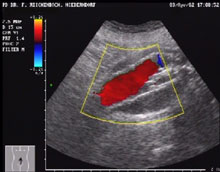

Die Funktion des Stents und die Rückbildung des Aneurysmas wird nach drei Monaten mit CT, dann halbjährlich sonographisch kontrolliert. Die Intergrität der Metallstents läßt sich auch mit einer einfachen Röntgenaufnahme des Abdomens kontrollieren.